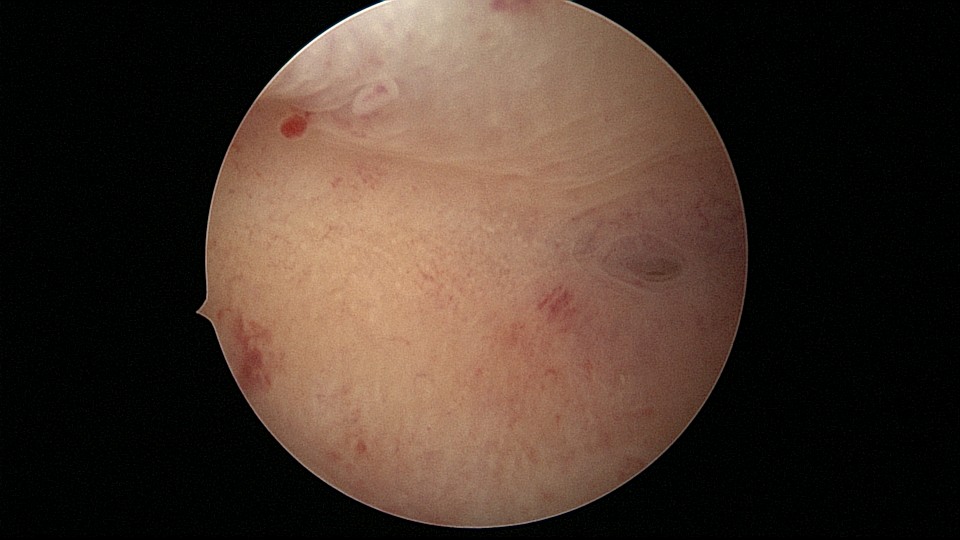

患者28岁,G1P0,2019年11月孕9周胎停1次,药流清宫,术后月经量逐渐减少,淋漓不净。外院B超发现宫腔粘连,2021年6月初宫腔镜探查,宫腔两侧及右侧宫角粘连,单级电针分粘,恢复宫腔形态,显露双侧输卵管开口(术中图像采集系统突发故障,分粘及分粘后图片未采集到)。2021年6月底宫腔镜二探取球囊,宫腔形态正常,双侧输卵管开口可见。2022年12月自然妊娠,足月顺产。现33岁,G2P1。